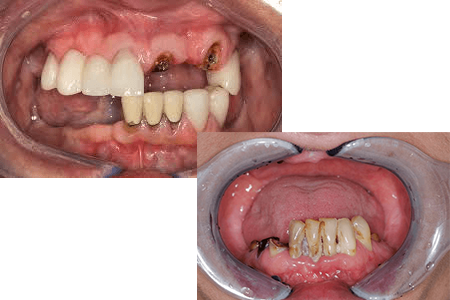

歯がボロボロ、ほとんどの歯が無い

残っている歯が重度の虫歯や歯周病で大きく揺れている場合、無理に残しても十分に噛めないことがあります。そのようなケースでは、オールオン4によってインプラントで固定式の歯を再建でき、しっかり噛めるだけでなく、見た目の改善にもつながります。

オールオン6・オールオン4の治療例

| 治療内容 | 上顎をオールオン6、下顎がオールオン4で治療しました。 |

| 費用 | <上顎>オールオン6 3,100,000円(税抜)、インプラント二次手術10,000円(税抜)、サージカルステント作製30,000円(税抜)、仮歯(プロビジョナルレストレーション) アバットメント無10,000円(税抜)×6・アバットメント有30,000円(税抜)×6 <下顎>オールオン4 2,700,000円(税抜)、サージカルステント作製30,000円(税抜)、仮歯(プロビジョナルレストレーション) アバットメント無10,000円(税抜)×8・アバットメント有30,000円(税抜)×4 CT撮影料10,000円(税抜) |

| リスク | インプラントは自由診療なので保険適用の治療と比べて治療費が高額になります。 インプラントが骨と定着するのを待つ期間が必要なので治療期間が長くなります。 手術後に腫れ・痛みが出ることがあります。 |